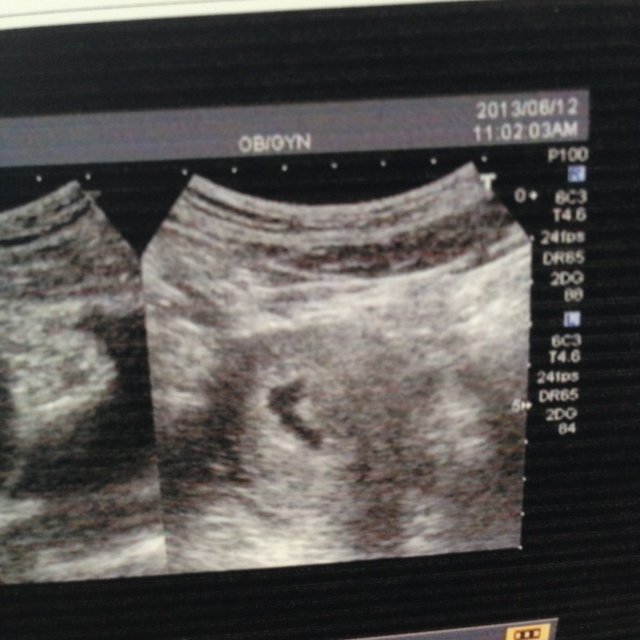

麻烦明白的帮看看什么情况,谢谢!超生所见:子宫前位,增大,宫内探及无回声囊,囊大小16x7mm 囊内未见明显胎芽及卵黄囊回声,囊形态欠饱满。 点击展开 匿名用户 2013-06-12 15:49 满意回答 这是妊娠几天的超声影像?如果是怀孕五周以内的最司指就不要担心,宝宝从第五周才开始长胎心,那时才能听到怠玻明显心管搏顿录动。建议十天或半个月后复查,或者结合血HCG和孕酮分析。 匿名用户 2013-06-12 15:59 宝宝知道提示您:回答为网友贡献,仅供参考。 相关问题 彩色超声诊断报告 超生所见子宫增大,肌壁间回声不均匀,宫内可探及大小约7乘7MM孕囊回声 超生波描述: 子宫前位增大,宫内可探及胎囊回声,大小2 2*1 6cm,囊内可见胎芽crl:0 6 超生所见: 膀胱中度充盈 子宫增大,水平位,宫腔内探及大小约34*20mm的妊娠囊回声,内可见一胎